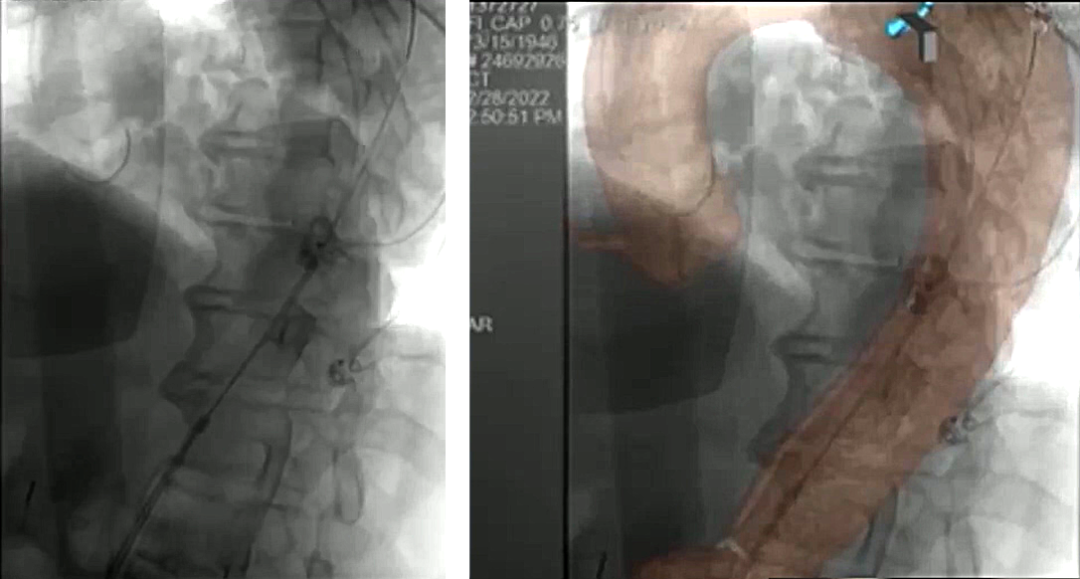

根据下图中的操作细节和结果可以得到的信息为:从出现症状到STABILIZE手术的间隔时间是9个月,可以看到使用球囊对覆膜支架下方的裸支架进行后扩张,改善贴壁并获得更好的定位。

根据下图数据,可以看到STABILIZE技术一个显著的并发症,也是我们必须要注意的地方:在球囊扩张过程中(不能在大于42毫米的远端动脉瘤上进行),会出现假腔血栓远端迁移。可能是因为影响了部分附壁血栓,并使其向远端移动。

2、下图为病例的影像图,可以看到支架的位置,受到压迫的真腔位置就在此处,通过影像图可以看到这里出现了内漏,必须进行处理;

3、进入假腔后可以看到真假腔中都有一根导丝。我们就可以将预先制作的Candy-plug沿导丝送入假腔。Candy-plug与支架保持平行,向上进入,将Candy-plug在这里释放;

4、我们需要在置入处放置22mm血管塞,放置位置需要准确及牢固。之后对真腔进行球囊后扩张,以此确保支架能够获得良好的封闭效果。